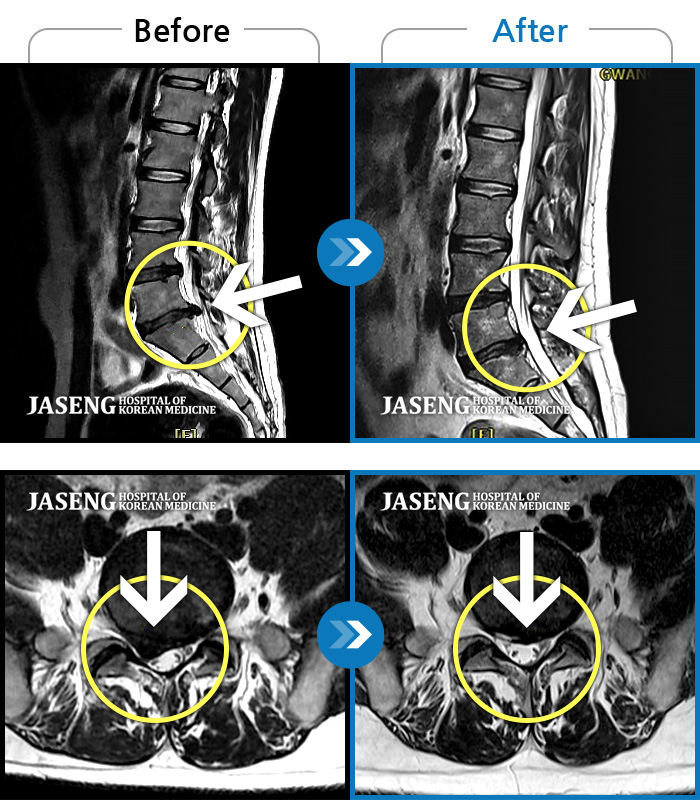

허리디스크

광주 · 김준수 원장

양측 허리에 묵직한 통증과 양측 허벅지부터 종아리까지 하지 방사통

촬영시기

2022.06.21 ~ 2022.12.24

2022.12.29

조회수 208